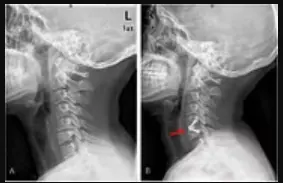

For millions of patients worldwide, spine surgery represents a beacon of hope for relief from chronic pain and restored mobility. Yet, when initial procedures falter—whether due to implant failure, infection, or unresolved pain—patients face a far more daunting reality: the need for Revision Spine Surgery Edison. Unlike primary operations, revisions navigate a minefield of scar tissue, altered anatomy, and the psychological weight of prior disappointment, often requiring surgeons to perform under the immense pressure of limited margins for error. Despite advances in spinal care, these second-tier surgeries remain fraught with complications, longer recovery times, and uncertain outcomes, leaving patients caught between the risks of intervention and the persistence of their original suffering. The challenge of addressing failed back surgeries isn’t just a clinical puzzle—it’s a silent crisis driving the search for solutions that reconcile technological innovation with the delicate art of spinal reconstruction.